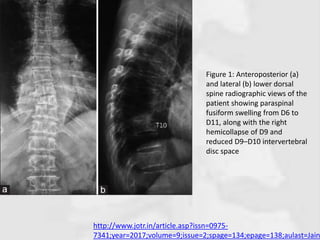

Figure 1: Anteroposterior (a)

and lateral (b) lower dorsal

spine radiographic views of the

patient showing paraspinal

fusiform swelling from D6 to

D11, along with the right

hemicollapse of D9 and

reduced D9–D10 intervertebral

disc space

http://www.jotr.in/article.asp?issn=0975- 7341;year=2017;volume=9;issue=2;spage=134;epage=138;aulast=Jain Figure 1: Anteroposterior(a) and lateral (b) lower dorsal spine radiographic views of the patient showing paraspinal fusiform swelling from D6 to D11, along with the right hemicollapse of D9 and reduced D9–D10 intervertebral disc space